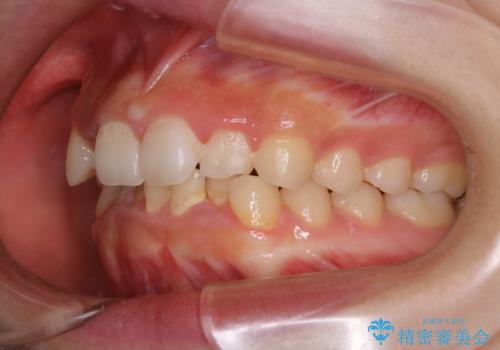

前歯のがたつきとディープバイト:インビザライン治療

- 前歯のがたつきと、噛み合わせが深いことを気にされてご相談にいらした方です。

インビザラインにて治療を行いました。

一般的に、歯冠(歯の長さ)が短い方はインビザライン治療に時間がかかりやすい傾向にあります。

歯の移動量に対して大きなブラックトライアングルもできることなく綺麗に並べることができ、大変喜んでいただけました。